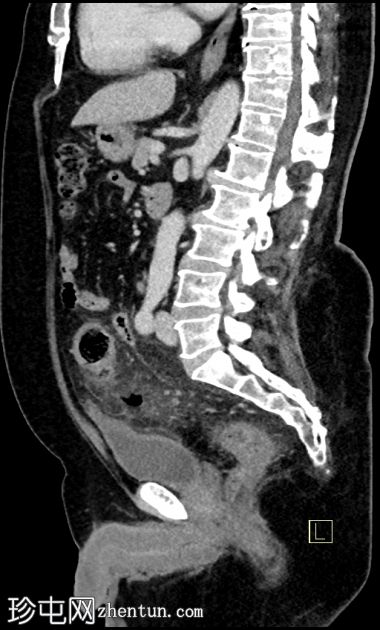

矢状位增强扫描(门静脉期)

3.jpg

多发性乙状结肠憩室。

乙状结肠壁增厚,伴结肠周围脂肪条索影,左侧壁局部穿孔。未见肠外脓肿、腹水或气腹,提示IA期复杂性急性憩室炎。

先前观察到的乙状结肠壁增厚和结肠周围脂肪间隙模糊进展,并新发现左侧结肠周围小软组织密度影(蜂窝织炎),大小为3.0 x 2.0 cm,可见中央气腔。该蜂窝织炎位于先前观察到的左侧壁缺损附近。

膀胱顶部反应性壁增厚。

未见气腹、腹水或腹腔内脓肿。

该病例表现出复杂性急性乙状结肠憩室炎的典型特征,伴有乙状结肠局部穿孔,提示为1A期复杂性急性憩室炎。患者接受了广谱抗生素保守治疗,1个月后因临床症状加重前来复诊。复查CT显示乙状结肠憩室炎恶化,出现结肠周围小蜂窝织炎,内含少量气腔。但未见弥漫性腹膜炎的征象,如腹水、气腹或弥漫性腹膜/大网膜混浊。之后患者失访。